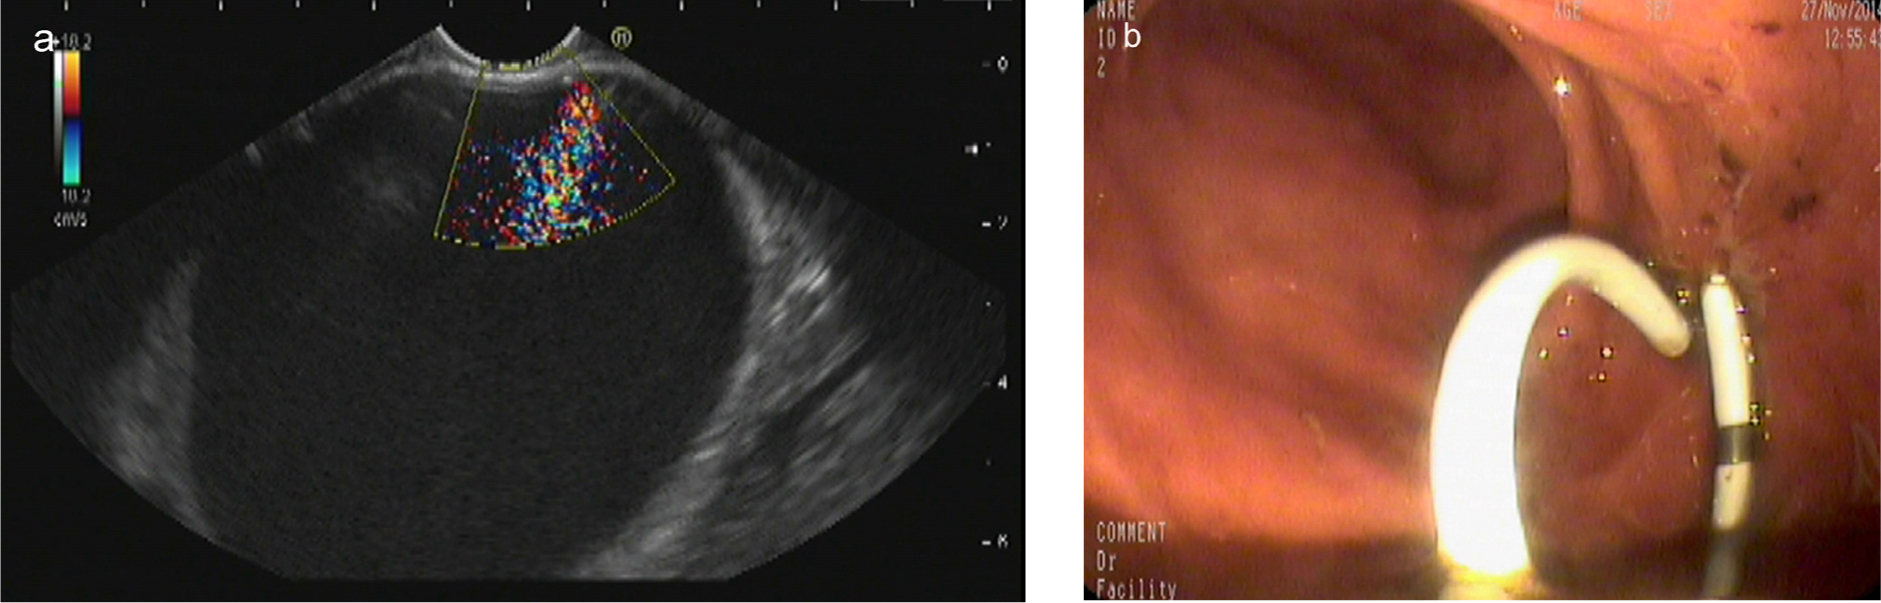

EUS-guided drainage process with plastic stent

The echoendoscope was introduced to scan the abdominal cavity for the pseudocyst and mark the puncture point. The contact zone (i.e., the closest approximation of the region between the gastric wall and cyst wall) was identified. Color Doppler was applied to identify the interposing vessels and thus avoid them during puncture. An EchoTip Ultra endoscopic needle was then introduced via the working channel of the echoendoscope, and the cyst was punctured under EUS guidance. A sample of the cyst was aspirated for biochemical, cytological, and tumor marker analysis. If the cyst was very small, this sample was limited to avoid rapid cyst deflation, which can cause increased difficulty during stent placement. The guidewire was inserted through the needle lumen into the cyst and coiled into 2–3 loops, and the needle was removed. The needle path was then dilated by the cystotome and a balloon dilator. A double-pigtail stent (10 Fr) was then introduced for drainage (Figure 1).

Endoscopic ultrasound-guided drainage process with plastic stent. (a) Pancreatic pseudocyst located at the body of pancreas; (b) a double-pigtail plastic stent was applied in the drainage.